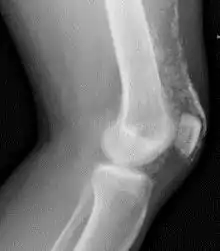

Magnetic resonance imaging may be useful to guide muscle biopsy and to investigate involvement of internal organs;[14] X-ray may be used to investigate joint involvement and calcifications.[15]